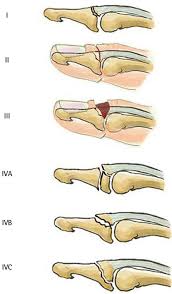

Mallet finger occurs when the extensor tendon becomes detached from the finger tip causing a drooped or deformed finger. Doyle's classification of mallet finger injuries. There is generally pain and bruising at the back side of the farthest away finger joint. This results in the inability to extend the finger tip without pushing it. Brooks and graner procedure for chronic mallet finger deformity. Dorsal extension block pinning is a commonly performed surgical technique for acute bony mallet fingers. Mallet finger occurs when the extensor tendon becomes detached from the finger tip causing a drooped or deformed finger. With mallet finger, the tendon on the back of the finger (not the palm side) is separated from the muscles it connects. There's an ongoing debate about whether surgery is better than splinting in complex cases. Mallet finger is a condition often seen after sports related trauma that causes the finger tip to droop, sometimes confused as a. However, most injuries that cause mallet finger do not cut the skin.) it may take several months for your finger to fully recover its function. A mallet finger results when the extensor tendon is cut or torn from the attachment on the bone. Mallet finger, also known as baseball finger, is an injury to the thin tendon that straightens the end joint the majority of mallet finger injuries can be treated without surgery.

By thomas trumble 50 videos. For simple closed mallet finger injuries, surgery is controversial. Mallet finger occurs when the extensor tendon becomes detached from the finger tip causing a drooped or deformed finger. The term mallet finger has long been used to describe the deformity produced by disruption of the terminal extensor mallet finger treatment & management. Mallet finger occurs when the tendon responsible for straightening the finger is damaged, leading to a deformity. And no, maybe is not too late. Doyle's classification of mallet finger injuries. Mallet finger is a condition in which the tendon in the outermost joint of a finger is ripped, causing surgery is rarely necessary for mallet finger.

Brooks and graner procedure for chronic mallet finger deformity. Most cases of mallet finger do not need surgery. Mallet finger can be due to disruption of the tendon alone or it can involve a small fragmentation of the bone. Doyle's classification of mallet finger injuries. Mallet finger injuries are usually treated without surgery, unless the injury is chronic.